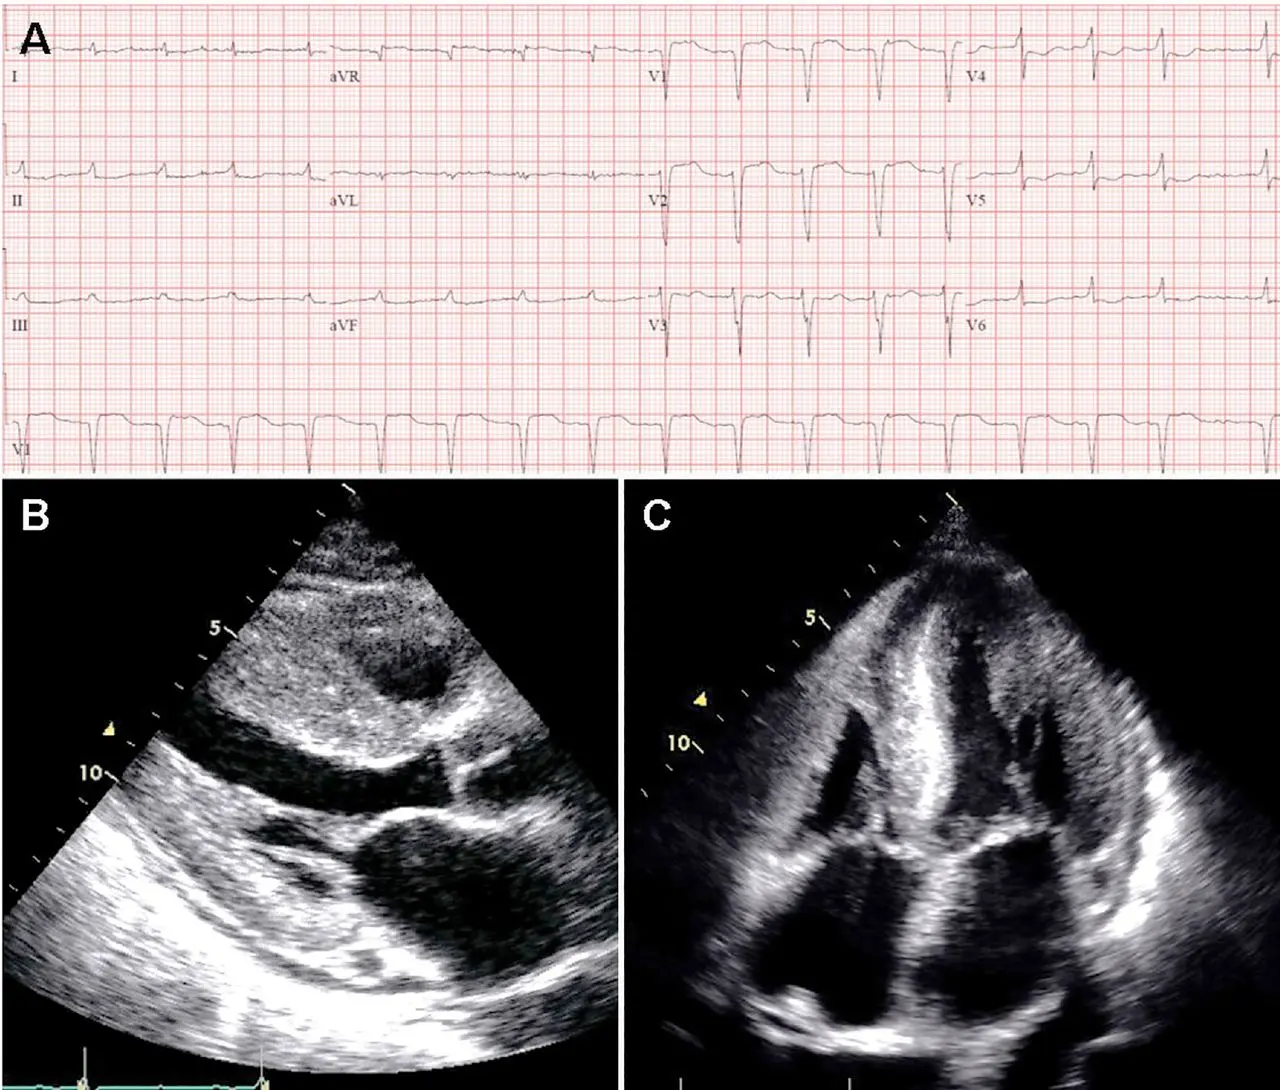

Discordance: LVH on Echo and Low-voltage on ECG

If you see LVH on echo but low-voltage on ECG, you should definitely suspect cardiac amyloidosis.

- ECG may show low-voltage and pseudo-infarct pattern (Q waves in early precordial leads, V1-V2) mimicking prior anteroseptal MI. 1

- 📝 only about 50% of patients with AL-CA and about 30% of patients with ATTR-CA meet true low-voltage criteria (QRS amplitude <5 mm in limb leads or <10 mm in precordial leads)

Echo:

- LV wall thickness >1.2 cm (0.6 cm to 1.0 cm is normal) in the absence of hypertension should prompt suspicion for CA. 1

- LVH is most commonly symmetric, but you may see asymmetric septal hypertrophy, particularly in ATTRwt-CA 1

- Strain Imaging with “apical sparing,” in which the apical LV segments have normal or near-normal strain compared with the mid and basal segments. 1